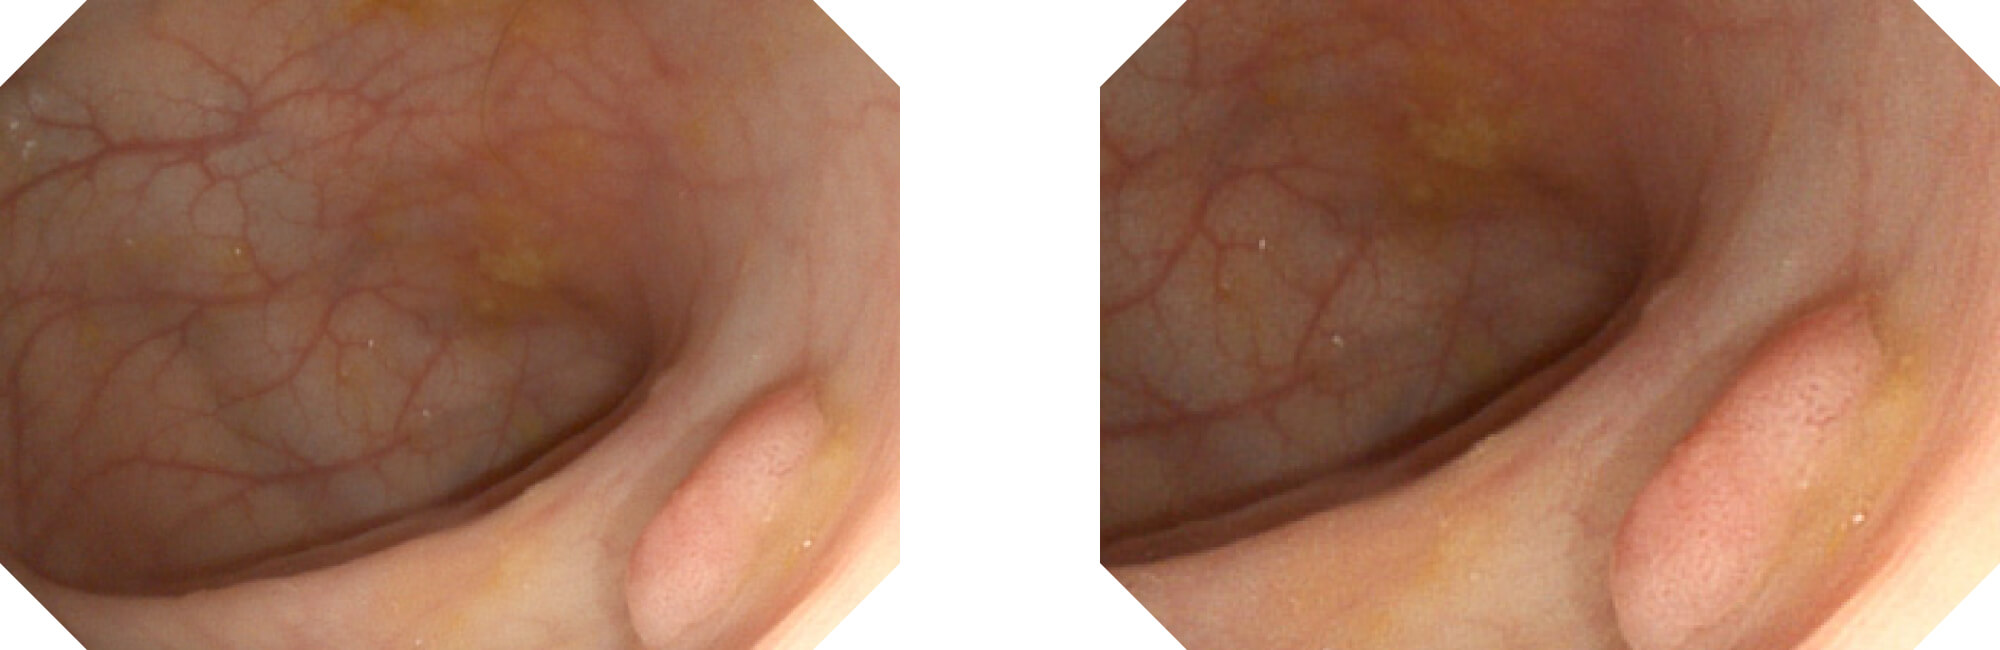

高清数字信号结合构造强调和色彩增强,多重图像处理技术能让每一个图像都清晰可见。

构造强调

色彩增强

电子放大

(Versatile Intelligent Staining Technology)

利用了血红蛋白在不同波长吸收下系数不同的原理,设计的一种光学域滤波和数字域滤波结合的染色技术,既保证了图像亮度,又可增强黏膜血管的对比度,充分凸显早期病变的细微结构变化,为临床疾病的观察诊断提供更丰富的参考信息。